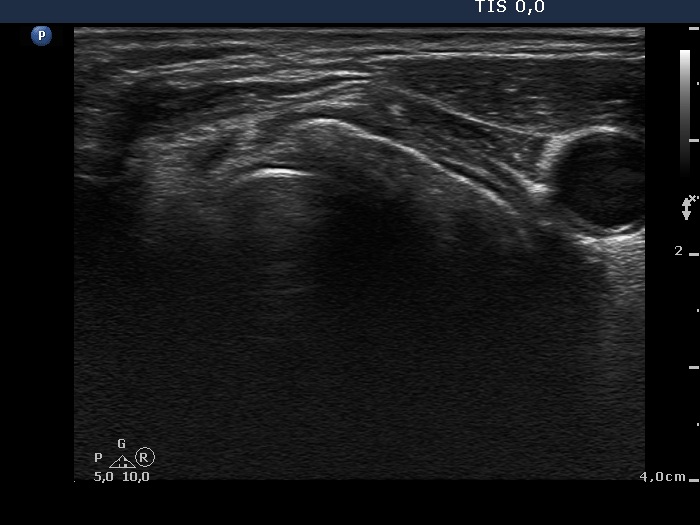

Thyroid cancers - case 529 (ultrasonographic picture 3)

Left lobe, transverse scan. This lobe has been also totally removed.